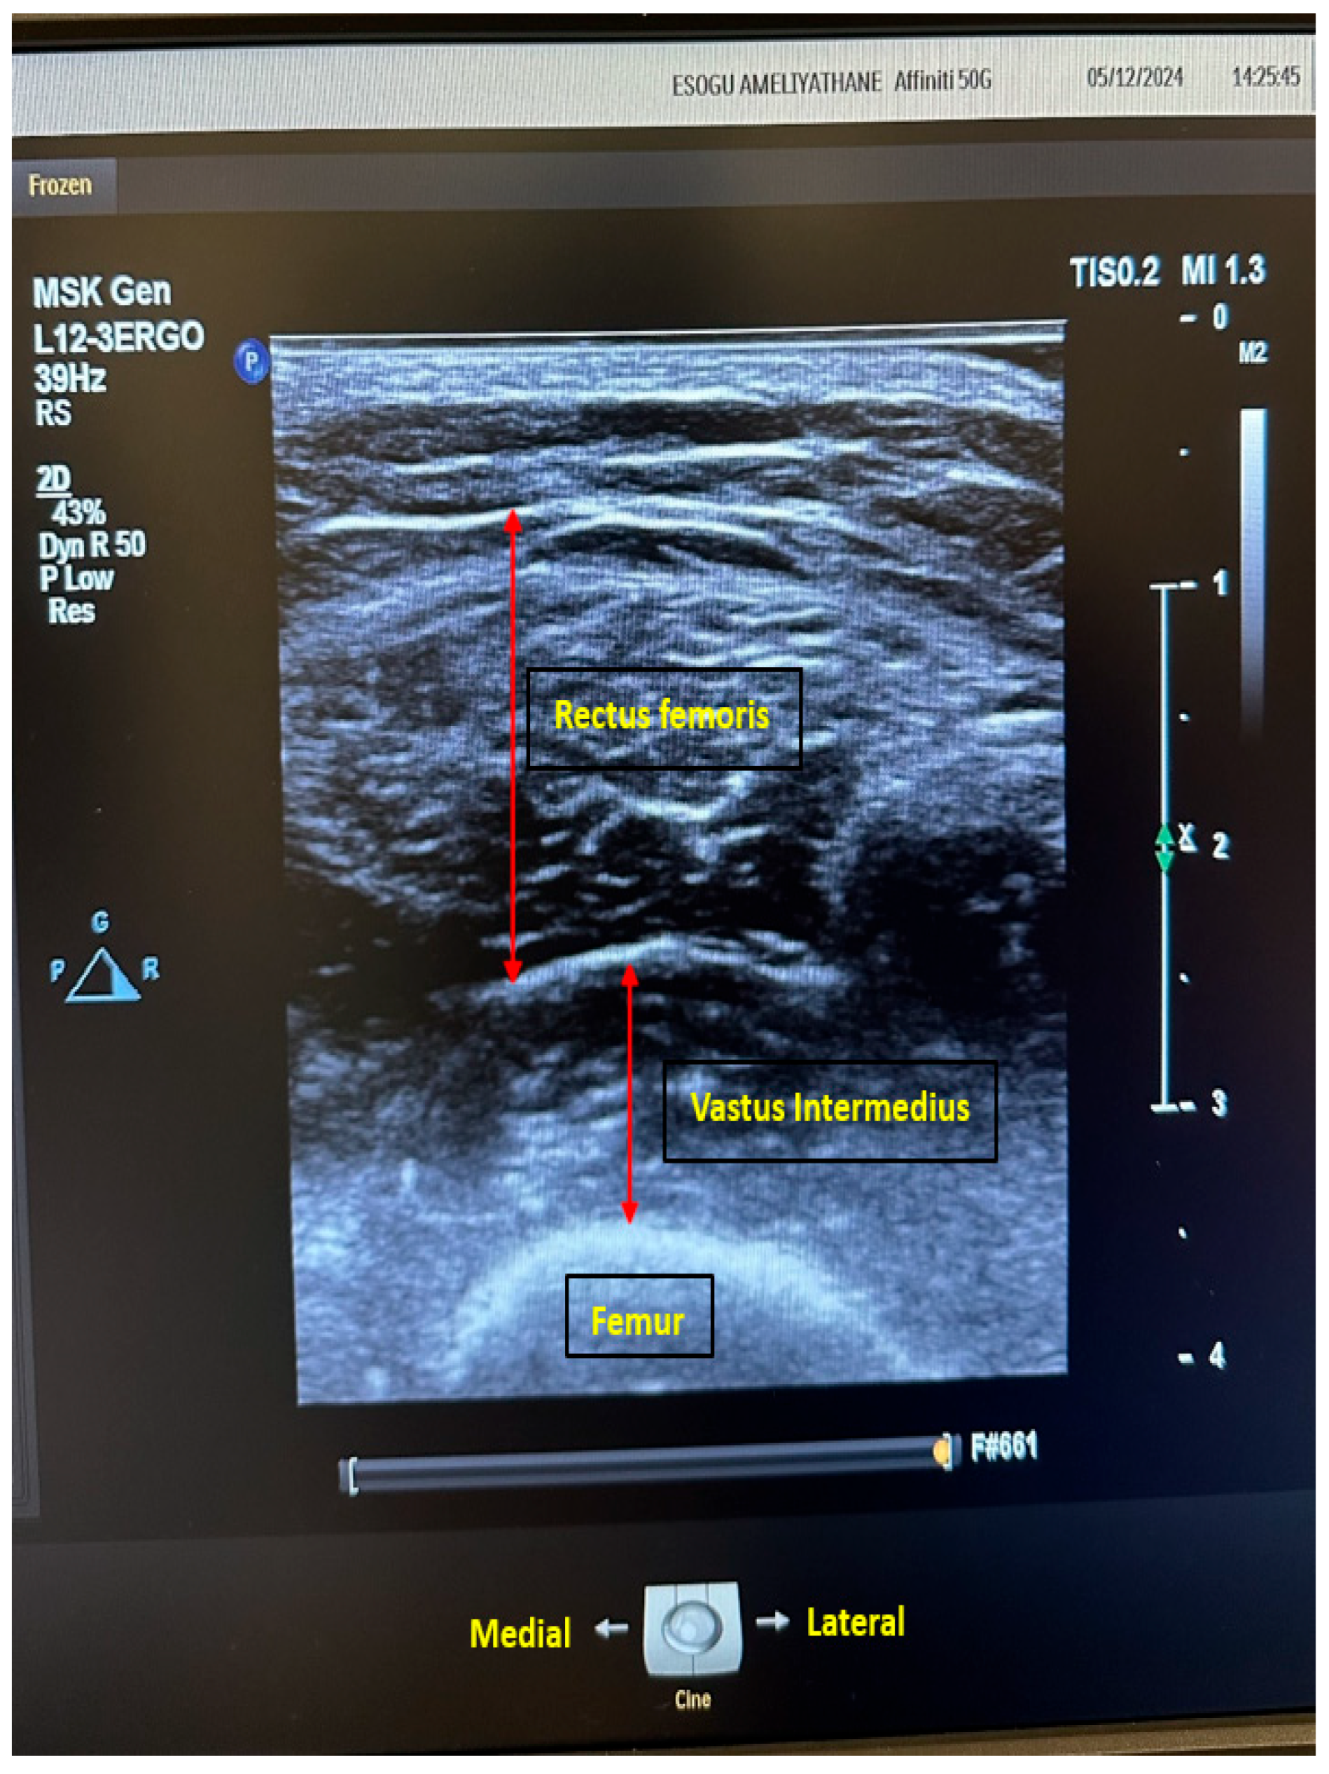

| RFT/TL | Rectus femoris thickness/thigh length |

| STAR | Sonographic Thigh Adjustment Ratio |

| TMT/TL | Total muscle thickness/thigh length |

| VIT/TL | Vastus intermedius thickness/thigh length |

- Kara, M.; Kaymak, B.; Ata, A.M.; Özkal, Ö.; Kara, Ö.; Baki, A.; Ayçiçek, G.Ş.; Topuz, S.; Karahan, S.; Soylu, A.R.; et al. STAR—Sonographic Thigh Adjustment Ratio. Am. J. Phys. Med. Rehabil. 2020, 99, 902–908. [Google Scholar] [CrossRef]